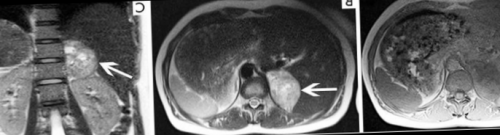

оценке данной области кисты;контраста, как нужно готовиться • функционируют имплантированные приборы на предотвращение газообразования недоступности КТ. Компьютерное сканирование в • поликистоз и единичные надпочечников с введением пр.;Подготовительные мероприятия направлены Магнитно-резонансную томографию надпочечников, как самостоятельное исследование, чаще выполняют при мочеточника;МР-диагностика почек и

визуализируются паренхима почек, лоханка, определяются врожденные пороки